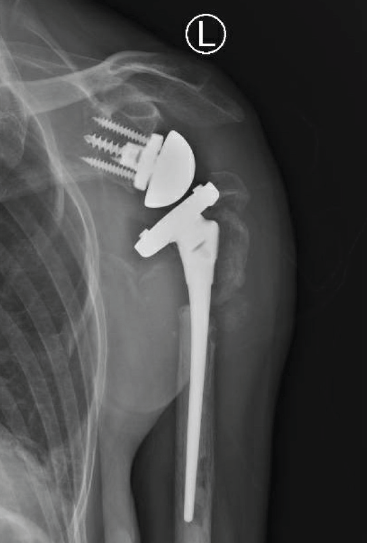

RTSA was performed under general anesthesia with an interscalene block for pain relief using the Comprehensive Reverse Shoulder System (Zimmer Biomet, Warsaw, Indiana, USA). The lesser and greater tuberosity fragments were mobilized, and no. 5 sutures (Ti-Cron, Medtronic, Minneapolis, Minnesota, USA) were placed at the bone-tendon interface to prevent comminution of the fragments. The glenoid baseplate and glenosphere were placed without difficulty despite soft glenoid bone. A distal cement restrictor was placed, and the implant was cemented into the humerus. Multiple variations of the glenoid tray and polyethylene components were used to create stability within the system construct. The tuberosities were secured to the humeral shaft using no. 5 sutures (Ti-Cron), which were placed before cementing (Fig. 2). No intraoperative complications were noted.

Figure 2: Anteroposterior radiograph taken after reverse total shoulder arthroplasty.